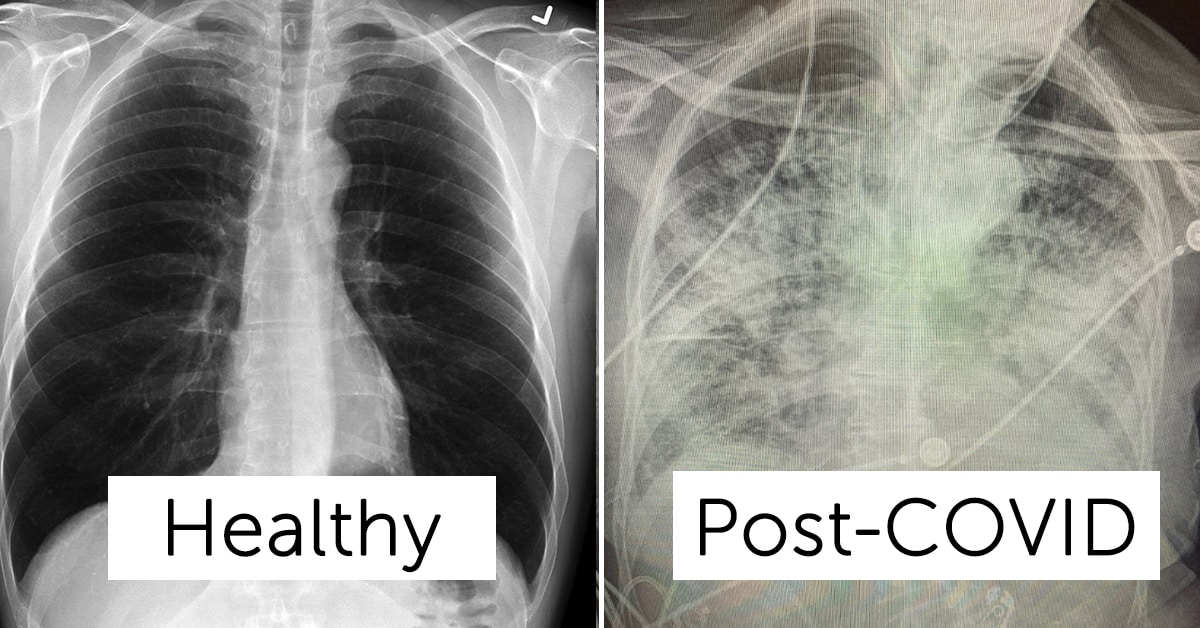

Here’s an example of a healthy lung that Dr. Bankhead-Kendall shared in a tweet:

More black space is a good thing. That’s the X-Ray passing through a healthy set of lungs.

Now, let’s see how much white scarring and congestion is visible on a post-COVID patient:

As you can see, there’s an intense amount of obstruction in the lungs of a post-COVID patient. More so than your average smoker. That’s how dangerous this disease is. I hope they start putting these photos on the windows of storefronts to encourage people to wear masks.